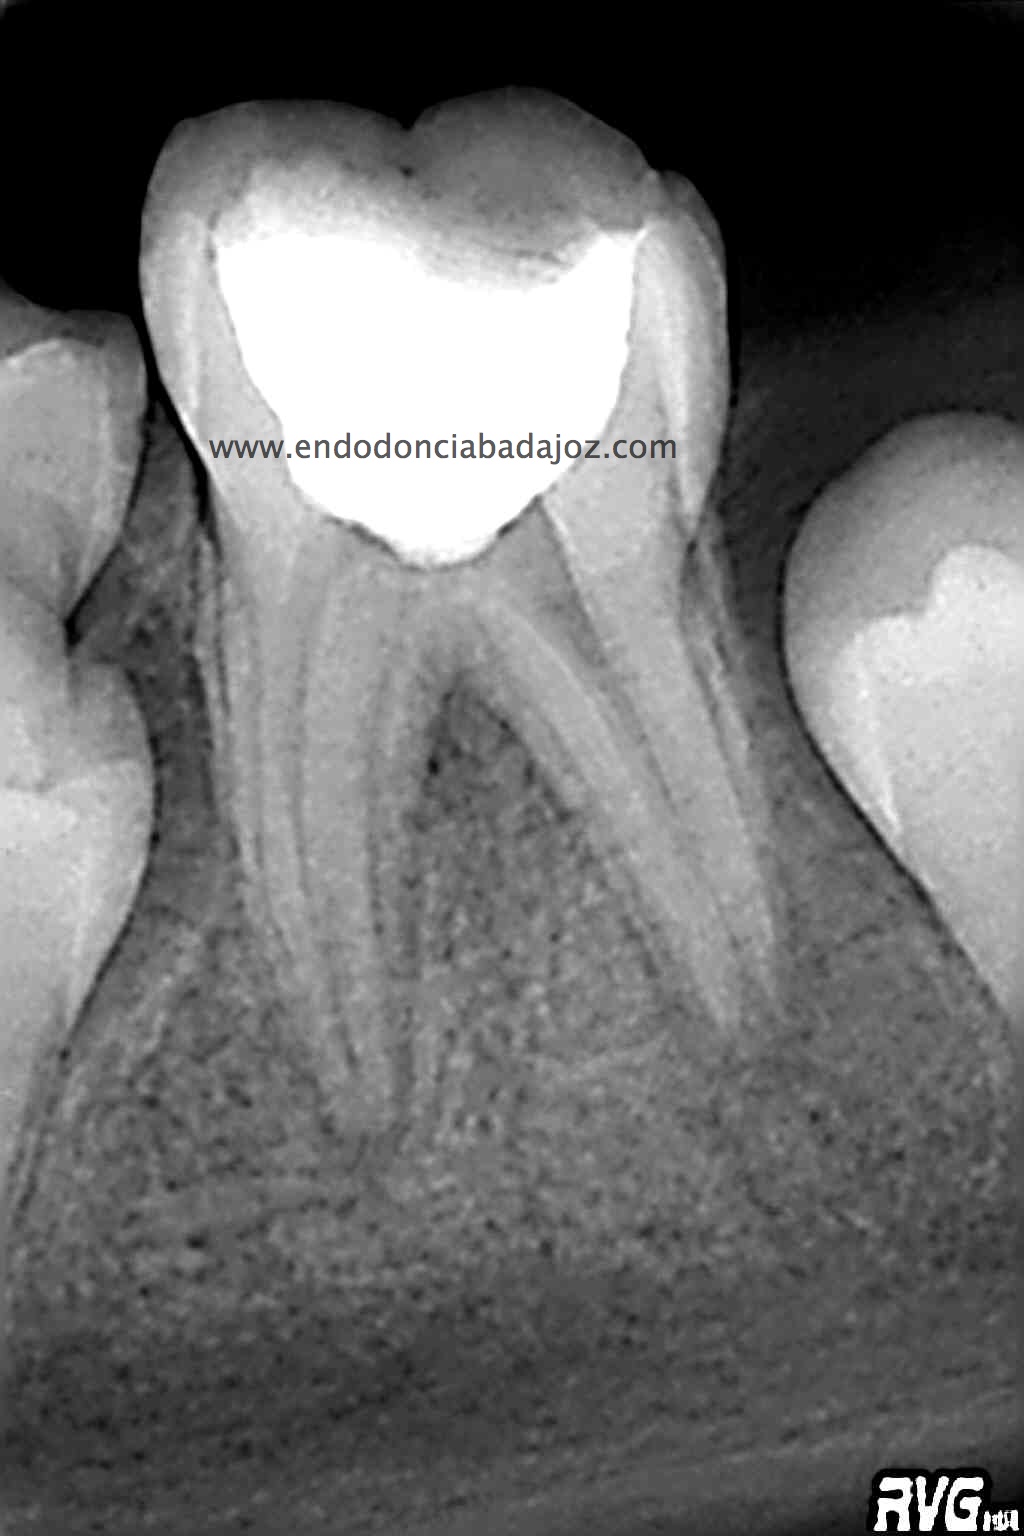

Para cerrar el año, propongo unos casos tres molares superiores:

A) Nos encontramos con un 1.7, con una necrosis pulpar con afectación periapical.

B) Un 1.6 con una pulpitis irreversible.

C) Por último, no encontramos un 1.6 con otra pulpitis irreversible.

Todos los casos los tratamos igual, con ayuda del microscopio, localizamos los cuatro conductos, instrumentamos con sistema Mtwo, y obturamos con sistema de condensación vertical con ola contínua para hacer el downpack y pistola Obtura II para hacer el backfilling.

Lo que tienen estos tres casos en común, y por lo que decido colocarlos, es por la importancia que tiene la irrigación, por que hay veces que aunque en molares superiores localicemos el conducto Mesio-palatino, puede que su salida se bifurque y nuestra lima no pueda seguir el conducto por que tiende a seguir recto uniendose al MV.